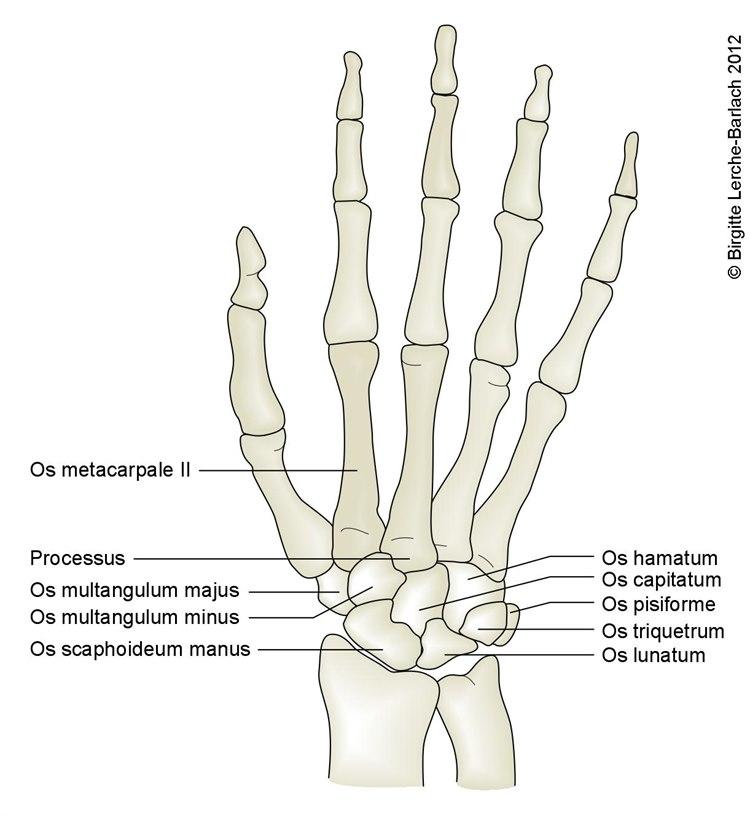

Underarmen består av to bein, spolebeinet (radius) på tommelsiden og albuebeinet (ulna) på lillefingersiden. Disse to beina holdes fast sammen av bindevev (syndesmose). Beina danner albueleddet sammen med overarmsbeinet (humerus), og håndleddet sammen med håndrotsbeina.